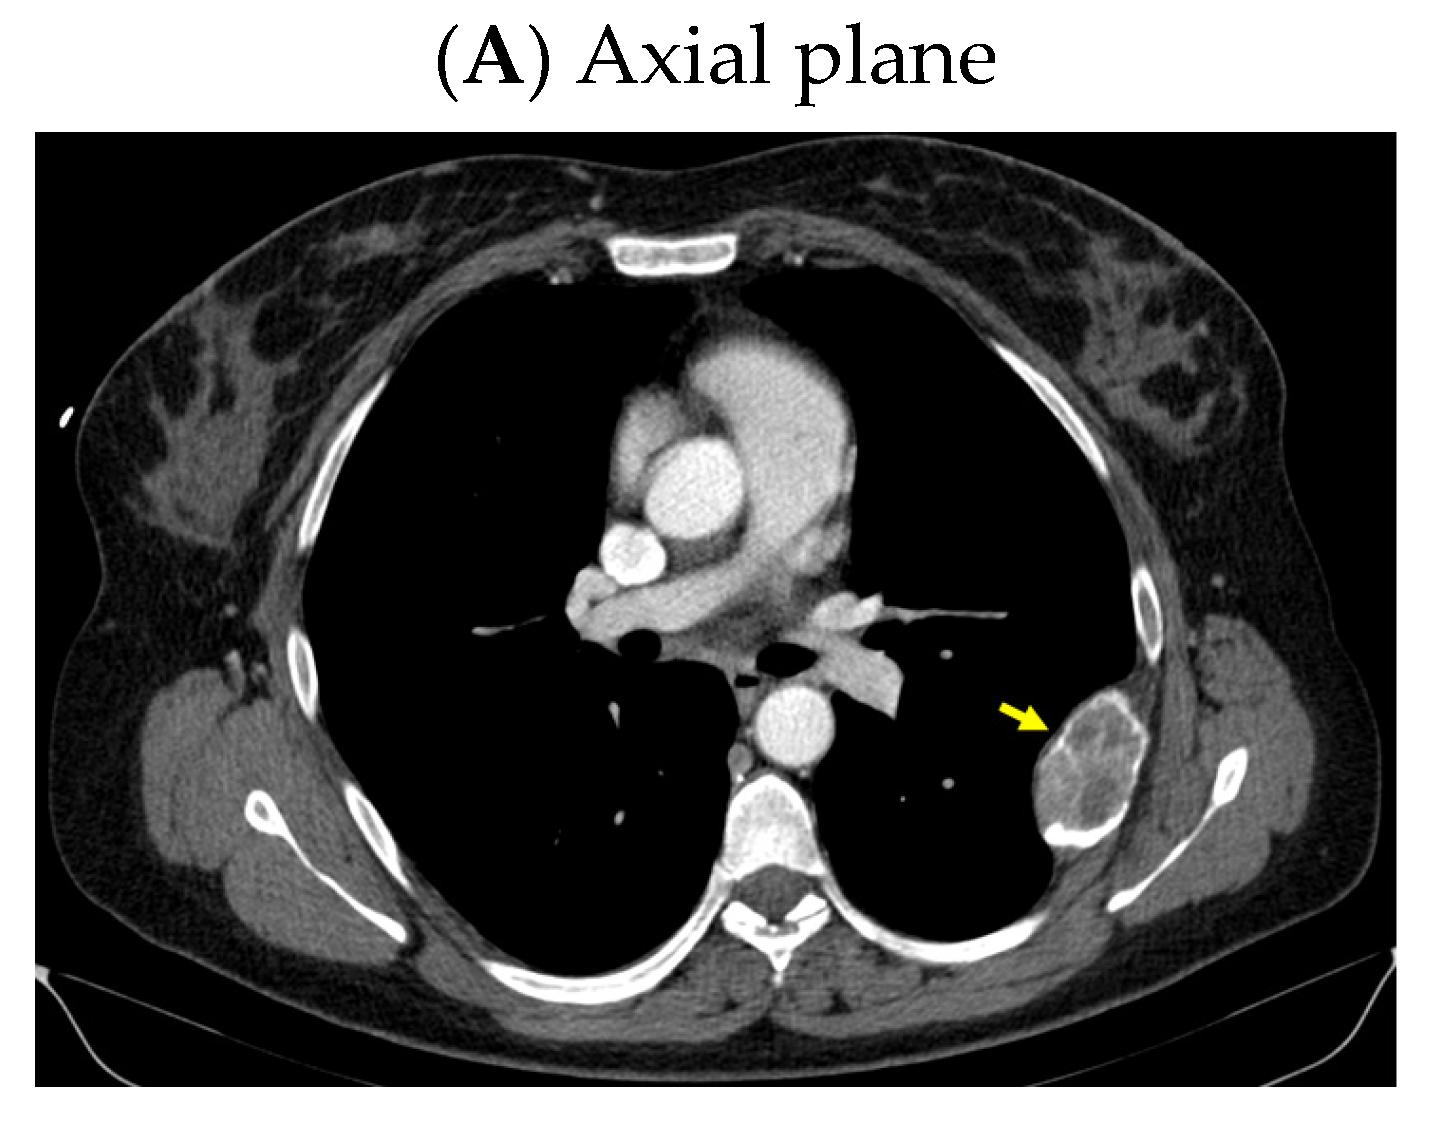

A CT scan confirmed the rib tumor mass (highly suggestive of a brown tumor) located in the middle and posterior part of the left sixth rib that caused median cortical destruction (of 3.09 by 5.13 cm in the axial plane, 2.53 by 3.31 cm in the coronal plane reconstruction, and 6.11 by 3.46 cm in the sagittal plane reconstruction) (Figure 5).

Figure 5.

Intravenous contrast CT: a tumor mass located in the middle and posterior part of the left sixth rib, with median cortical destruction of 2.53 by 3.31 cm, suggestive of a brown tumor (yellow arrow).

A pelvis CT scan confirmed the osteolytic lesions of the ischium and of the left coxal bone adjacent to the acetabular fossa, measuring 1.97 by 3.29 cm and 1.14 by 1.71 cm, respectively (brown tumors) (Figure 6).

Figure 6.

Pelvis CT scans showing other brown tumors: (A) osteolytic lesion of the left coxal bone adjacent to the acetabular fossa of 1.14 by 1.71 cm (axial plane); (B) osteolytic lesion of the left ischium of 1.97 by 3.29 cm (axial plane).